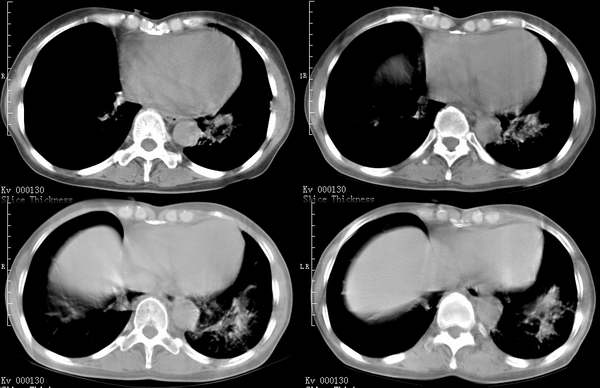

咳嗽6月低热1月!

右上肺和左下肺见有斑片状及条片状影,边缘模糊,纵隔内无肿大淋巴结,结合病史考虑肺结核可能大。

两肺纹理增粗,右上和左下肺可见肿块影,呈空泡征,分叶征。纵隔内无肿大淋巴结。考虑为肺瘤可能性大。

右上叶背段及左下叶见斑片状密度不均模糊影,右中叶支气管狭窄,中叶密度增高,体积缩小.纵隔未见明确淋巴结.结论:1、两俩结核,右中叶支气管内膜结核,并中叶肺不张。2、两肺炎;右中心型肺癌,并阻塞性肺不张。

右肺上叶尖后段及左肺舌叶 下叶见斑片状密度不均模糊影,右中叶支气管狭窄,中叶密度增高,体积缩小.纵隔未见明确淋巴结。考虑:双肺结核伴右侧中叶不张。

右上叶背段及左下叶见斑片状密度不均模糊影,右中叶支气管狭窄,近端未见肿块,中叶密度增高,体积缩小.纵隔未见明确淋巴结.结论:两肺结核,右中叶支气管内膜结核,并中叶肺不张。肺纹理粗乱,有慢支表现,伴有感染存在。

ct显示病灶呈多灶性分布,主要分布在双肺上叶后段,右肺中叶及左肺下叶,右肺上病灶内可见点状钙化,纵隔内示淋巴结钙化,结合病史6个月伴低热,考虑感染性病变,结核可能大.